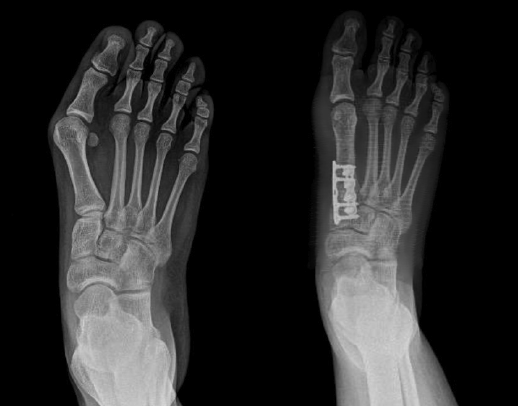

Figura 1. Representación de la ubicación del center of rotation of angulation (CORA) 1 (primera articulación tarsometatarsiana) y del CORA 2 (primera articulación metatarsofalángica).

Por lo tanto, el CORA lo debemos entender desde una visión tridimensional, ya que si analizamos solo el plano transverso para su corrección caeríamos en una interpretación simplista de un problema complejo(8,9,10)(Figura 1).

Figura 2. Artrodesis de Lapidus en 3D.

En trabajos más actuales, estos conceptos fueron apoyados por Lee(18), Klaue(19), Faber(20), Klos(21), Hatch(22) y Dayton(23), entre otros autores (Figura 2).